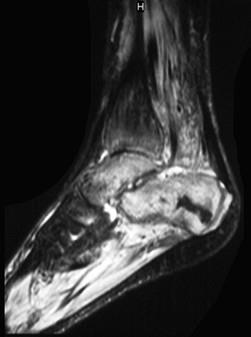

问题 男,28岁,踝部肿痛,结合图像,最可能的诊断是 ( ) .

选项 A、跟骨结核 B、踝关节类风湿关节炎 C、跟骨骨髓炎 D、踝关节滑膜炎 E、未见异常

答案 C